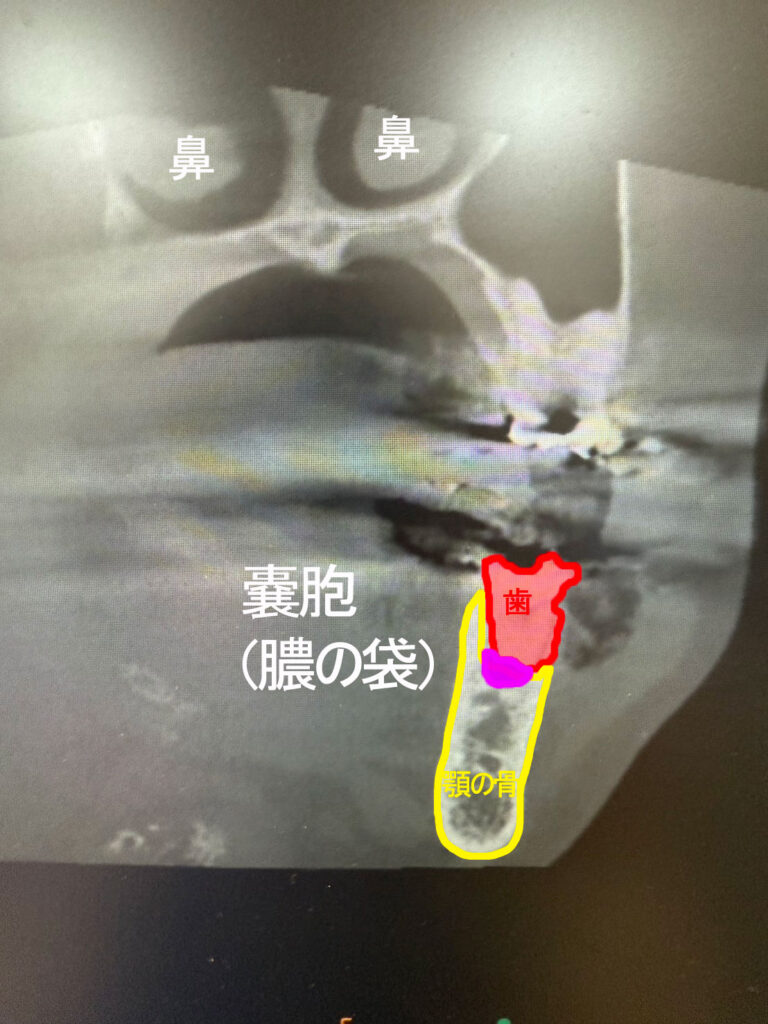

木更津きらら歯科では三次元画像が得られる歯科用CT(Computed Tomography-コンピュータ断層撮影)を導入しています。嚢胞の位置や骨への影響などをより正確に把握することができます。

こちらは歯科用CTで撮影したお口の中の断面です。赤い部分が歯、黄色の部分が顎の骨の断面です。ピンク色の部分を見てください。この患者さまは、歯の根っこに膿みが袋状にたまっていることがわかります。このケースでは歯を残すことができそうです。感染した根っこの部分のみを切除(歯根端切除術)し、同時に嚢胞を摘出します。

3D画像で撮影可能な歯科用CTです。レントゲンでは確認できない立体的な病変の広がり、位置関係、骨の状態、神経の位置などを精密に把握できるため、歯根端切除術などでは、正確で安全な治療を可能にします。